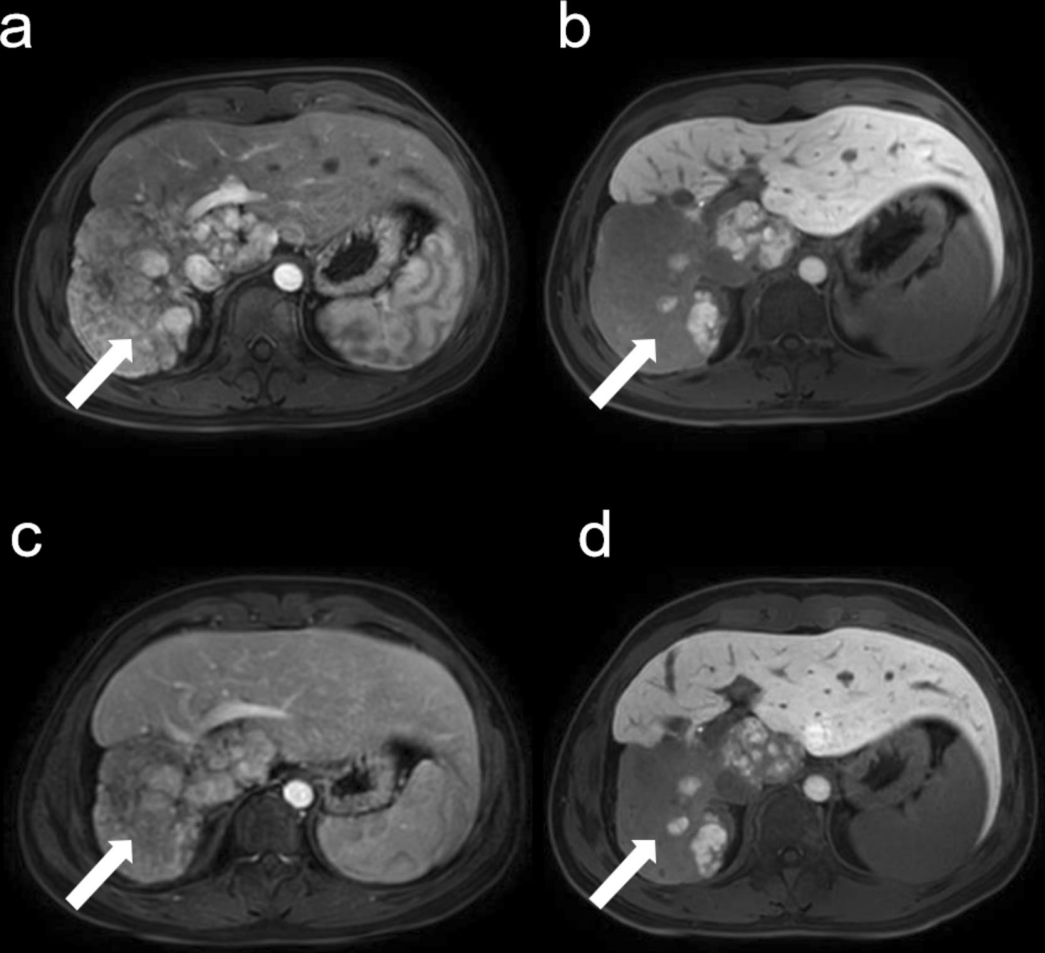

图为术后6个月,肿瘤大小85*113*124 mm,

动脉期呈低信号(a),肝胆期呈低信号(b)。SIRT后9个月,

动脉期持续呈低信号(c),肝胆期持续呈低信号(d)

小星在手术半年后,病变缩小至85×113×124毫米,且大部分病变已坏死(图a、b)。治疗后9个月的随访显示,病变的大小和强化程度进一步降低(图c)。患者上腹部饱胀及进食受限症状已缓解,体重恢复。